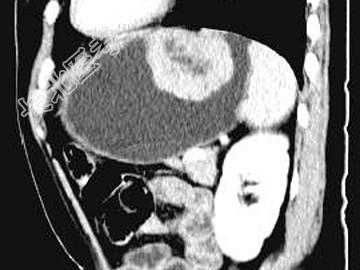

- 单项选择题女,51岁, 上腹部隐痛不适,CT检查如图, 最可能的诊断是 ( )

A、胃癌

B、胃息肉

C、胃腺瘤

D、胃溃疡

E、胃间质瘤